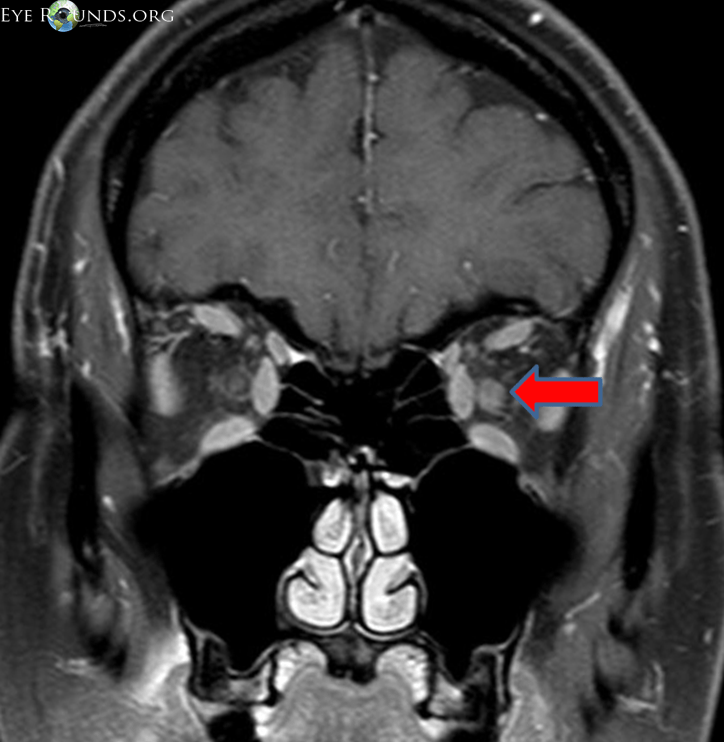

From www.eyerounds.org

Optic neuritis from one medical student to another medical student Optic Disc Neuritis Recurrent episodes of on indicate a propensity toward developing. Optic neuritis (on) may involve the retrobulbar (retrobulbar neuritis) or the intrabulbar (papillitis) portion of the optic nerve,. Optic neuritis is an inflammatory, demyelinating condition that causes acute, usually monocular, visual loss. Optic neuritis (on) is one manifestation of central nervous system inflammation with resultant demyelination. Optic neuritis is a broad. Optic Disc Neuritis.